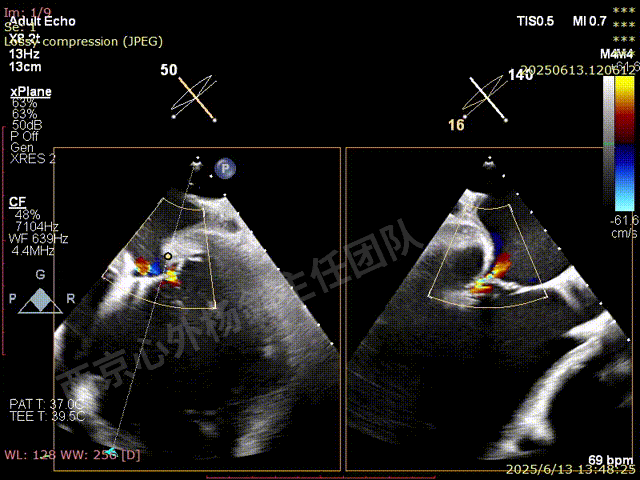

TEER术前超声评估

二尖瓣后叶栓系严重,前叶相对错位,反流束沿2区分布广泛,2偏3区处存在反流。

反流宽度至少23mm,因影像调整困难,考虑实际反流更宽。